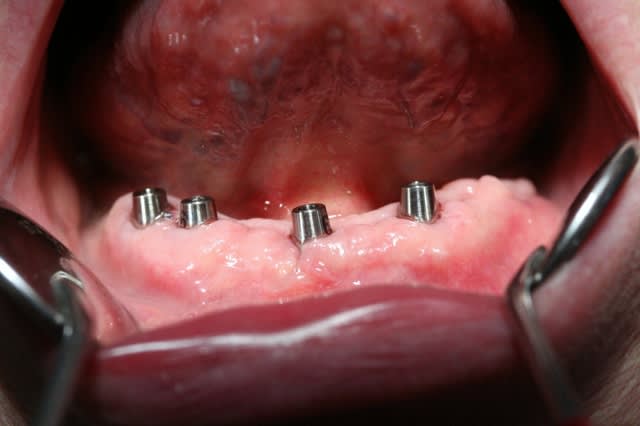

des photos si vous voulez...

photo 10 ; on voit les parties femelles qui sont posée sur les piliers . on décharge le complet au niveau des piliers, un peu de résine, remettre en bouche, faire mordre, quelques mouvements et le tour est joué!

les parties femelles restent dans le complet (qui peut être le complet d'usage du patient) et la stabilisation est immédiate.

il faut au mini 4 implants en bas et en haut 4 à 6.